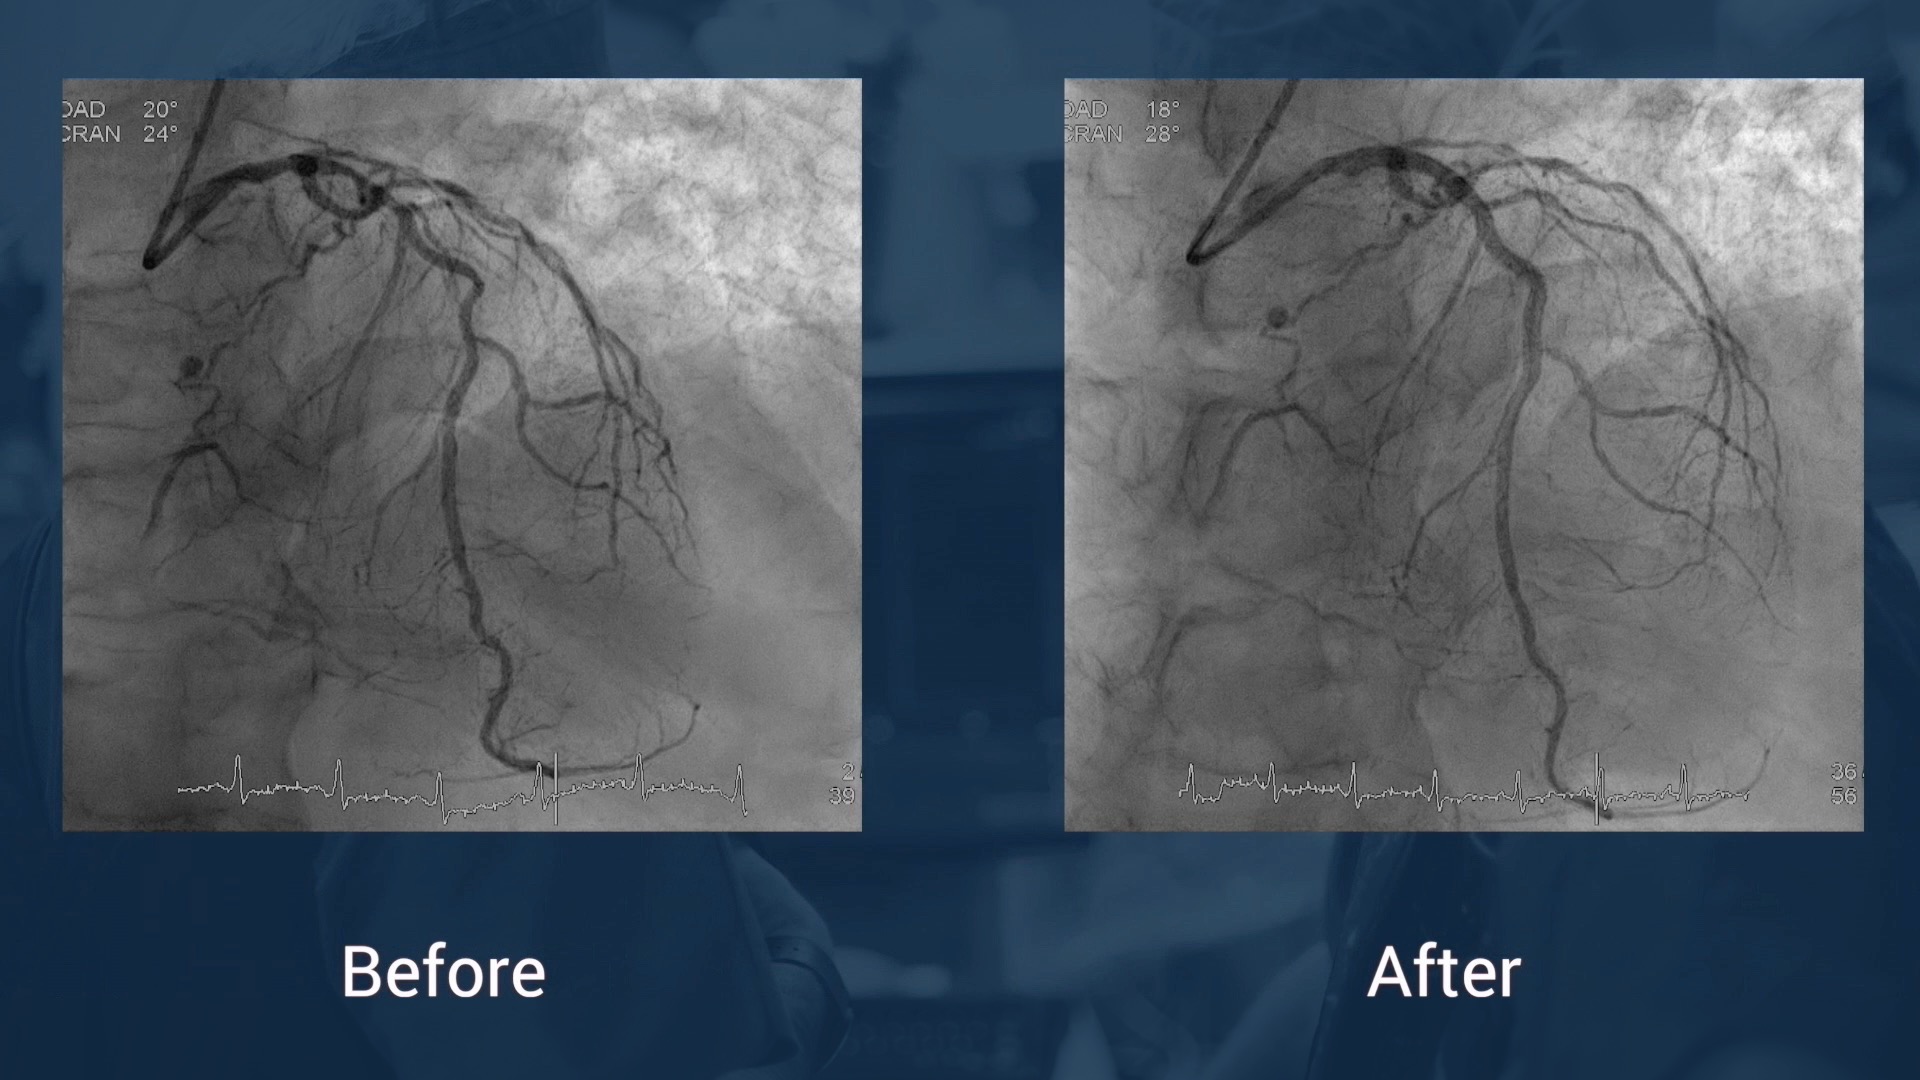

• Preoperative coronary angiography (AVF)

• Optimal lesion preparation with rotational atherectomy.

• Rotational atherectomy.

• Stent implantation Xience Alpine